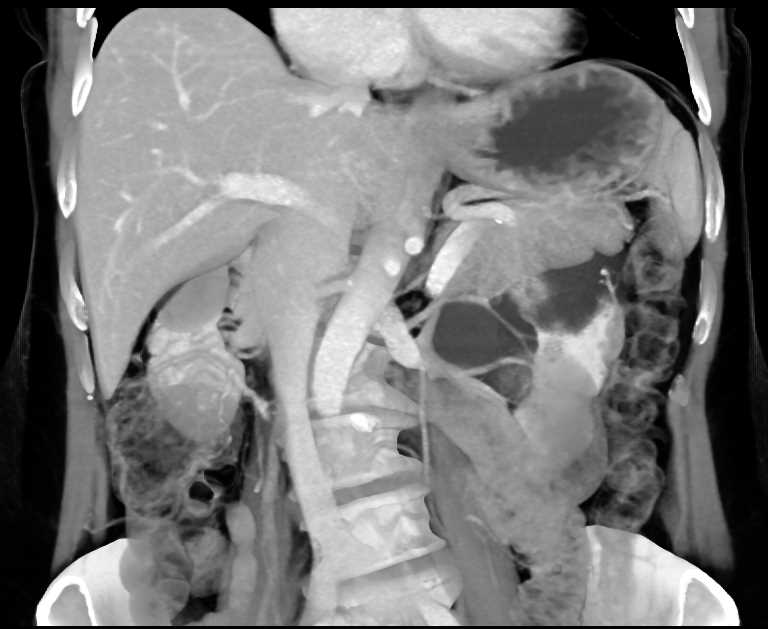

Parapelvic Cysts Left Kidney